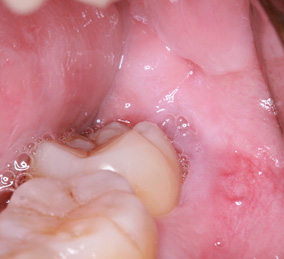

親知らずの歯根の先端と下顎神経が近接している場合は2回に分けて抜歯を行うことがあります。まず、親知らずを2分割して頭の部分を抜きます。その後しばらく期間をおいて、のこる歯根の部分が頭を抜いたスペースに移動したのを確認して抜きます。

このように2回に分ける事で安全な抜歯が可能です。

当院で処置した2回法による親知らずの抜歯について詳細を下記よりご覧いただけます。

※歯肉の切開、出血を伴う写真がございます。

2回法親知らずの抜歯処置を表示する

まず歯冠を切除し、疼痛がでないよう、冠部歯髄を除去してネオダイン(歯髄の鎮痛鎮静、象牙質の消毒、覆髄)を填入します。その後、粘膜骨膜弁にて完全閉鎖を行います。以下に処置の流れを示します。

歯冠切除量と歯根の移動量の結果です。術前の智歯(親知らず)の幅径に対して計測した智歯の長径の割合は1.21ポイント、術後は1.10ポイントで有意に差を認めました。数ヵ月待機することにより歯根は有意に近心側に移動していることを認めました。